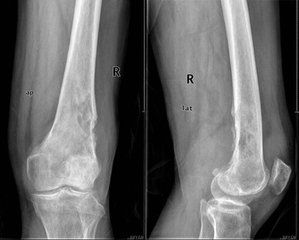

2.好發部位骨惡性纖維組織細胞瘤在骨骼上的分布與骨肉瘤類似。主要侵及長管狀骨骨端(約為全部病例的75%)。下肢骨較上肢骨更容易發病,其比例約為6∶1。股骨(約45%)、脛骨(20%)、肱骨(9%),是腫瘤最常見部位。髂骨發病約占10%,其他發病部位是顱骨和面骨(4%)、肋骨(3%)。腓骨、脊柱、肩胛骨和鎖骨是不常發病部位。侵及手、足小骨者罕見。

在長管狀骨中,腫瘤位於乾骺端,且經常伸展到骨骺或骨幹,或兩者兼有之。膝關節周圍骨的發病率約為在長管狀骨的全部腫瘤的50%。